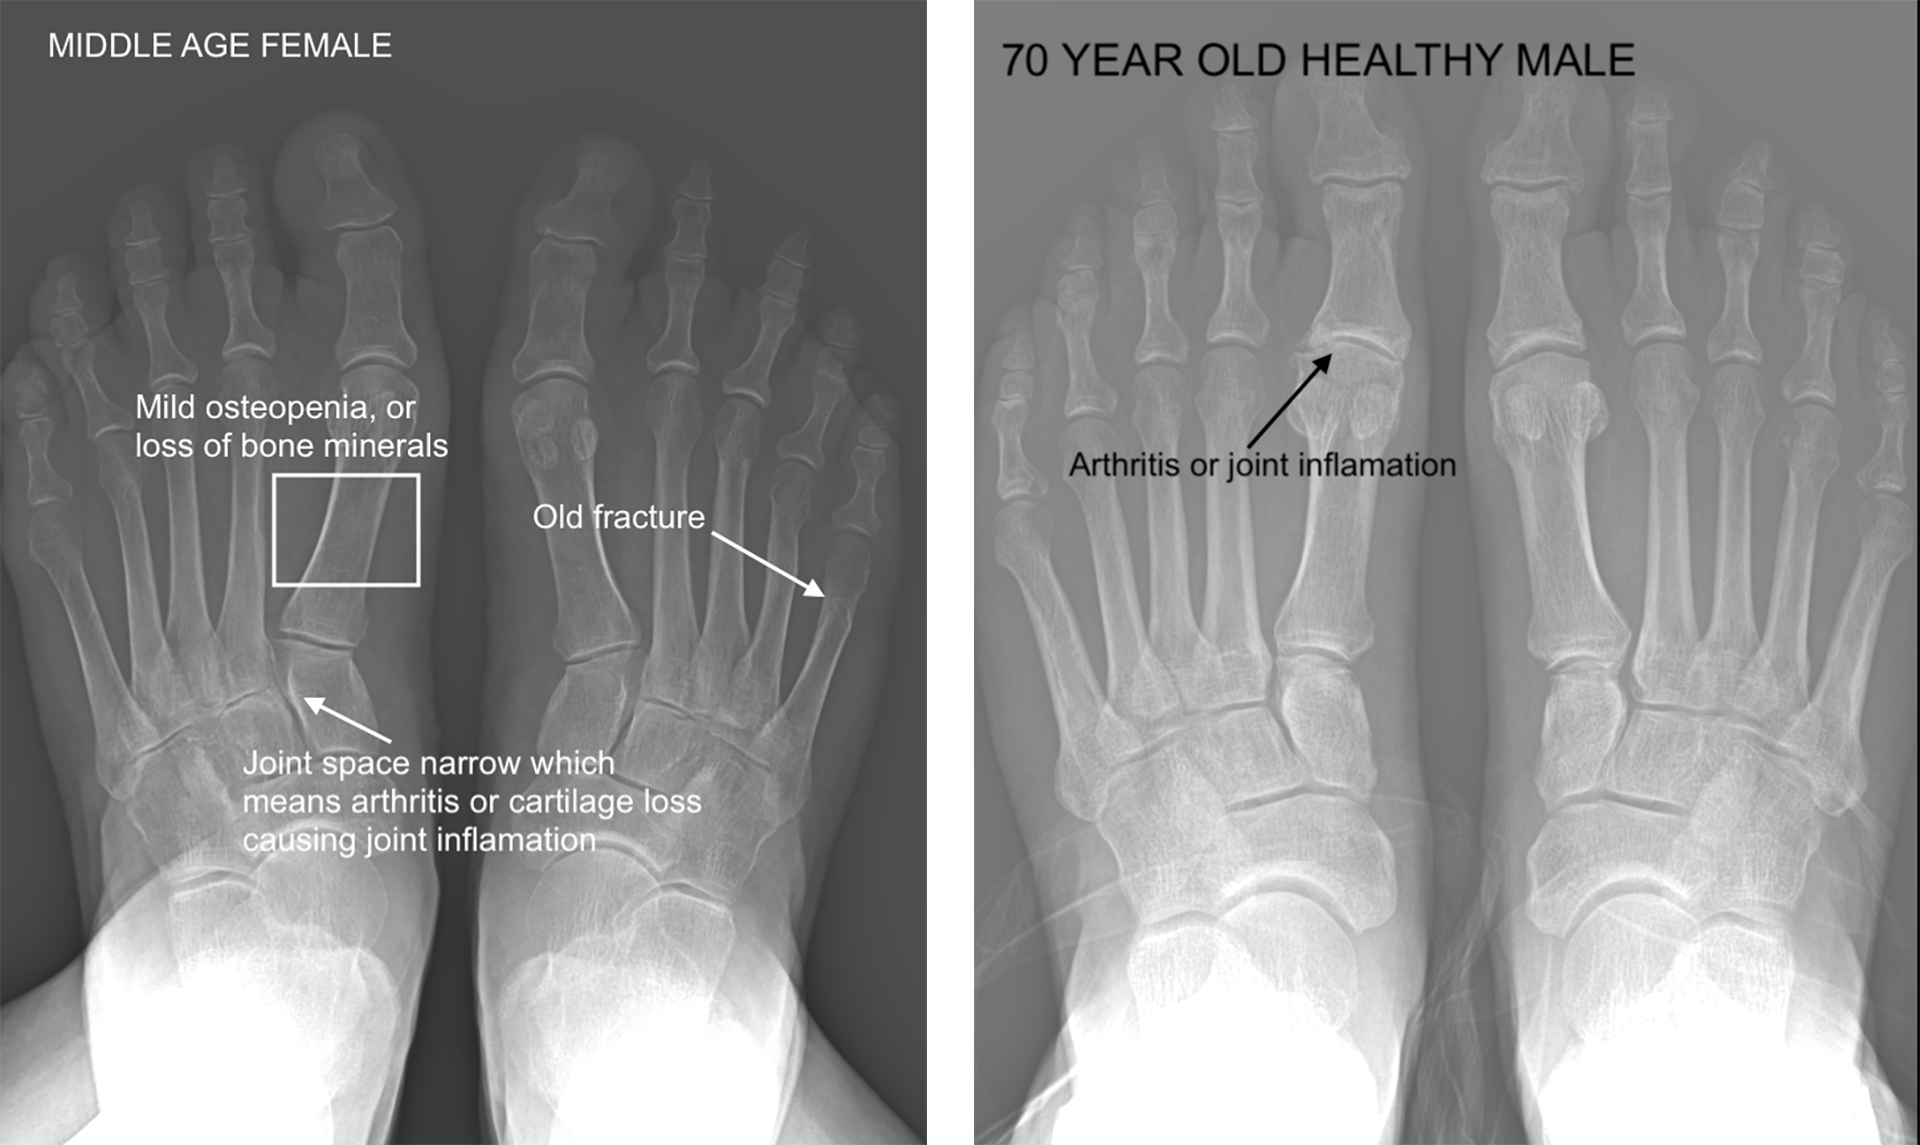

DIAGNOSTIC X-RAY

Is it true that a picture says 1,000 words. In the case of an x-ray, YEP! In-office x-ray is very helpful to assess fractures, foreign bodies, clogged arteries, arthritis, and growth plate patterns and injuries. It is important to get this real-time picture for a most accurate picture of what is actively going on inside your feet and ankles. Even a few days can make a big difference in images, so doing an x-ray in our office at the time of your appointment is the most accurate to the diagnostic process.

As we age, it is typical that we see your bones become less dense. Bone mineral density loss is normal as we age, but everyone is different and will experience density loss at different rates. On an x-ray, the whiter & lighter the bone looks, the healthier the bone matter is. Adversely, on an x-ray, the more grey the bone the less dense and more susceptible to fractures and arthritis.

In children, we want to see a healthy growth plates, cartilage (as opposed to bone) and healthy tendons and ligaments to understand if they are growing at a steady rate. X-rays help us determine how to design an orthotic around a foot type to help prevent or relieve pain in the natural aging process, determine if a fracture needs surgery, if its a broken bone or arthritis causing pain.